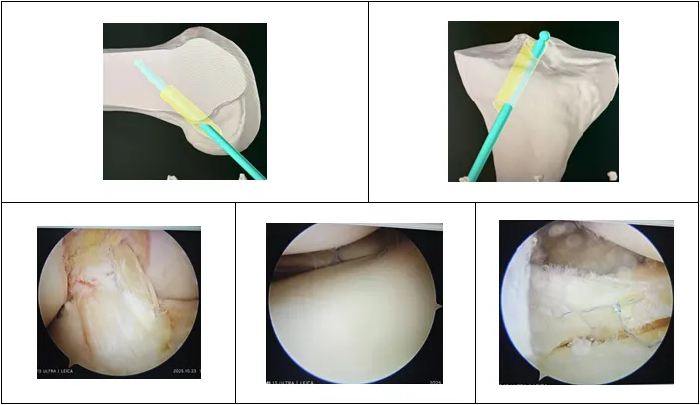

术中操作:

参照术前规划进行机器人辅助下精准定位

术后即刻评估:

影像、镜下评估与稳定性测试良好

术后第二天复查影像:

MRI、三维CT重建显示重建韧带位置及张力良好